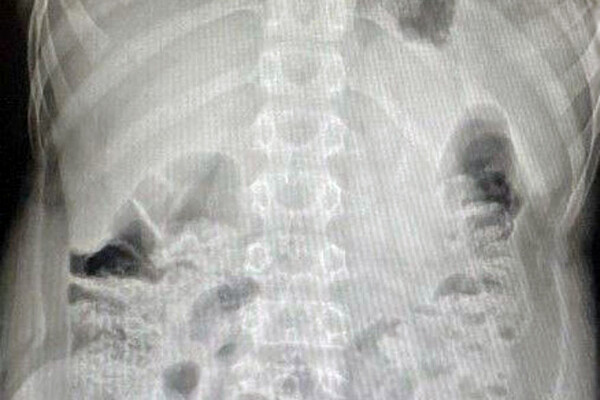

В медучреждение 12-летнего пациента привезли родители. Они рассказали, что сын проглотил батарейку из пульта от телевизора. Между моментом инцидента и обращением за помощью прошло очень мало времени. За это время инородное тело успело опуститься в слепую кишку. Врачи приняли решение о немедленном извлечении предмета.

«Вначале выполнили лапароскопию, чтобы визуализировать как возможные осложнения, так и расположение инородного предмета. Затем провели эндоскопическое исследование, во время которого с помощью специальной петли извлекли литиевую батарейку», — поделился детский хирург, заведующий хирургическим отделением №1 Игорь Хворостов.